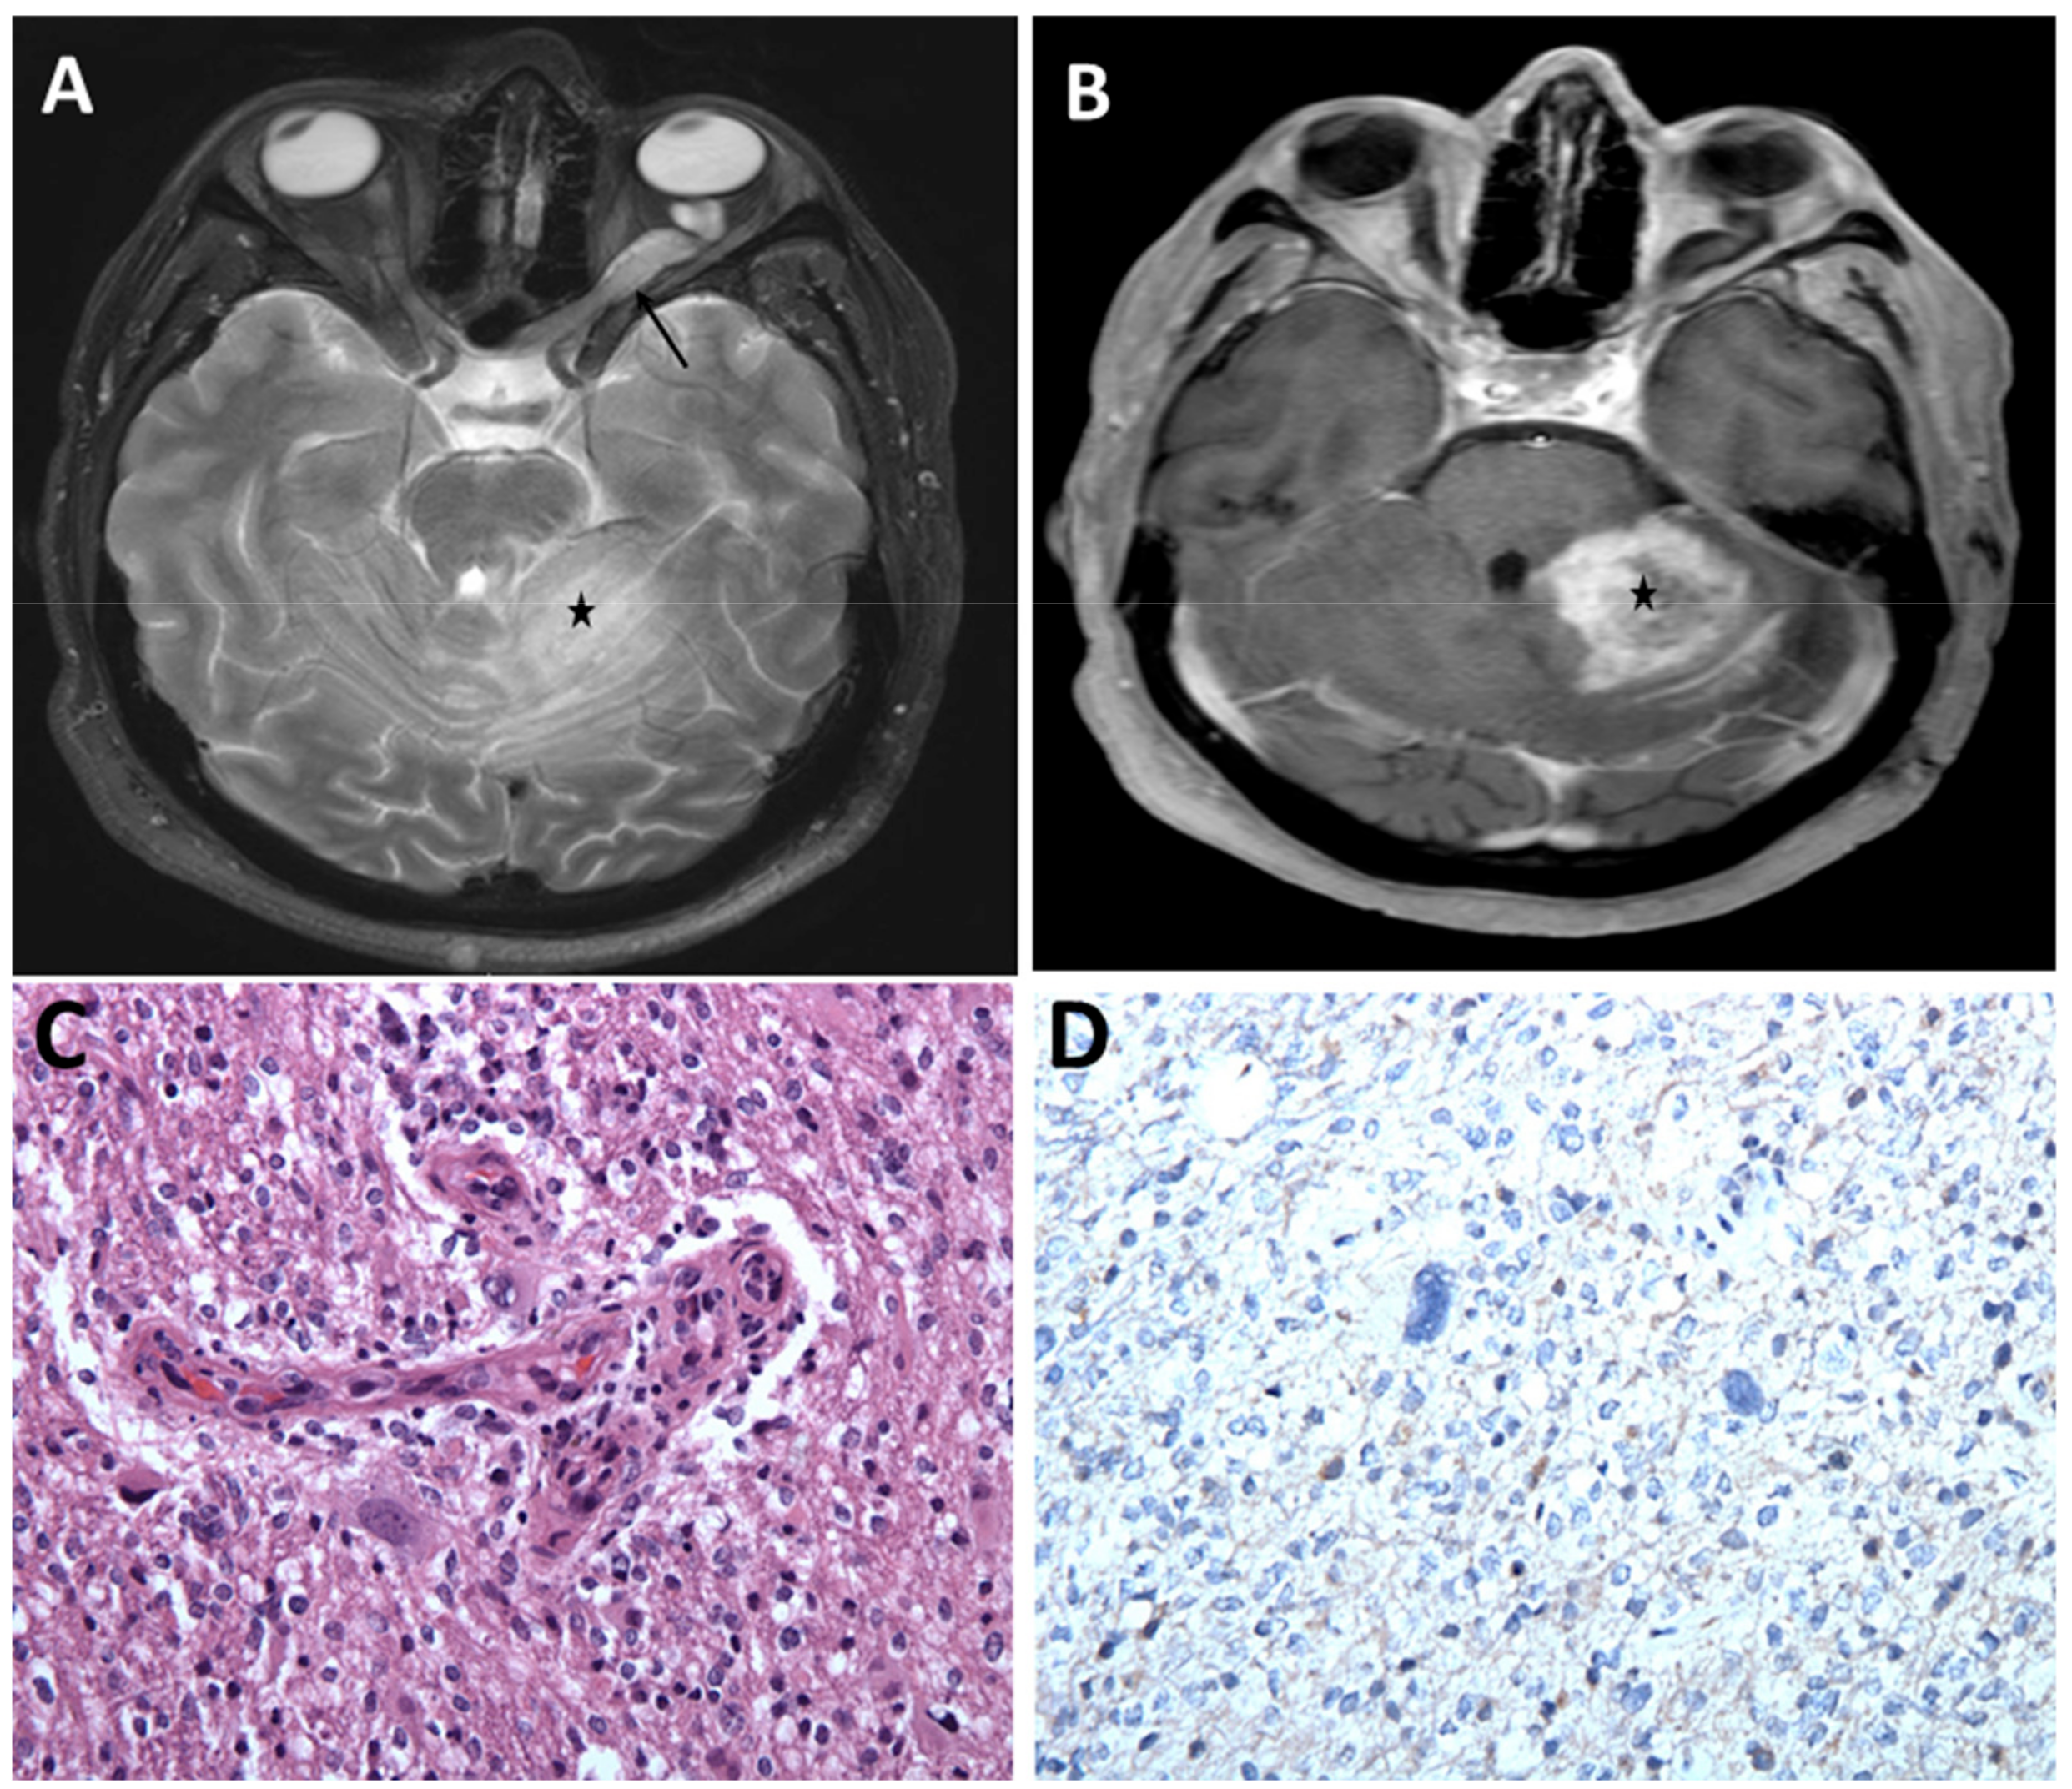

- Narasimhaiah, D.; Sridutt, B.S.; Thomas, B.; Vilanilam, G.C. Glioblastoma in Adults with Neurofibromatosis Type I: A Report of Two Cases. Neuropathology 2019, 10. [Google Scholar] [CrossRef] [PubMed]